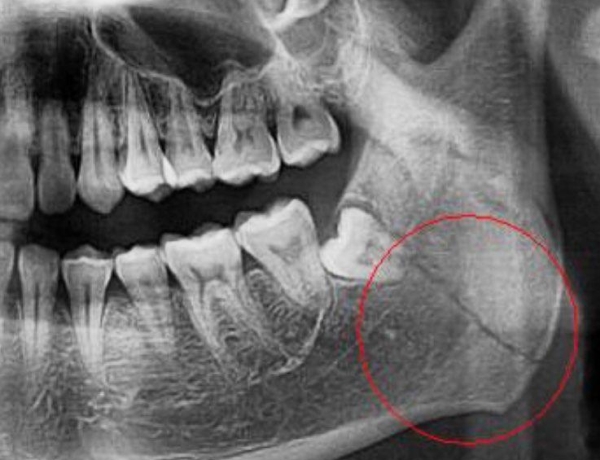

Перелом нижней челюсти врач может определить по внешним признакам, а также с помощью прощупывания, которое позволит определить место перелома. Для получения боле точной информации обязательно потребуется рентгенологическое исследование. Важно помнить, что сильный удар, вызвавший перелом челюсти может спровоцировать еще и сотрясение мозга или кровотечение в полость черепа.